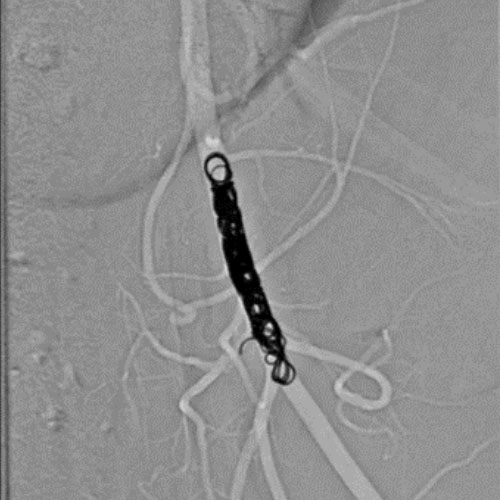

Embold Fibered Coil shown in left internal femoral artery Ruby Standard Coil shown in left internal femoral artery

Left Internal Femoral

Artery

5 Ruby Standard 6x20

Embold Fibered Coil shown in right internal femoral artery Embold Fibered Coil shown in right internal femoral artery

Right Internal Femoral

3 Embold Fibered Coil 6x20

5 vs 3 Coils